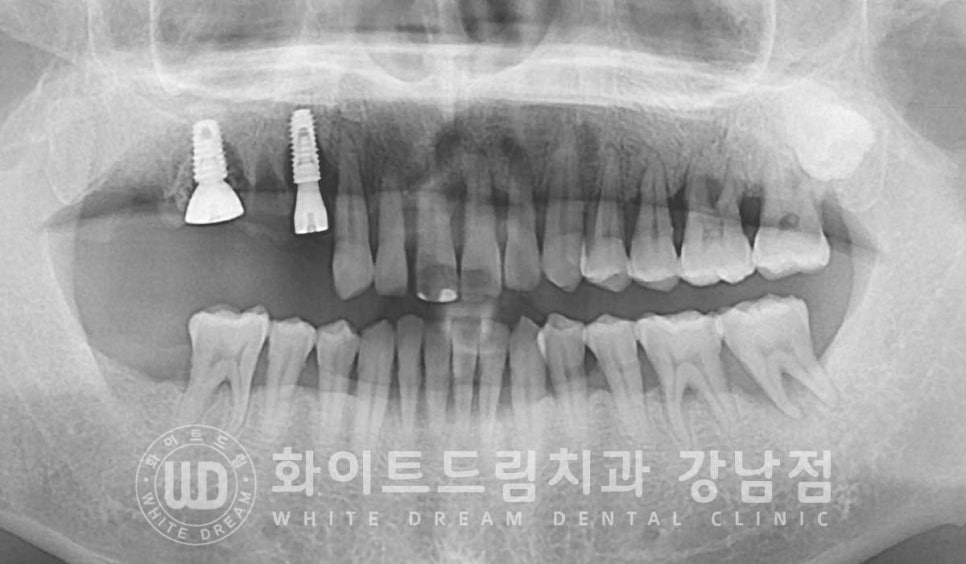

환자분의 초진 x-ray 사진입니다.

전체적으로 잇몸뼈가 치주염으로 크게 내려앉아있는 상태로

치료가 필요한 부위가 많이 있으나

한 번에 치료를 진행하기보다는 천천히 하나씩 진행하길 원하셔서

우선적으로 불편함을 크게 호소하셨던 10번대 어금니부터 치료를 진행하고 계신 분입니다.

10번대 치아 주위 잇몸뼈를 보면 검은색으로

치아 뿌리 주위에 동그랗게 표기된 부분이 보일 겁니다.

x-ray 상에서 밀도가 낮을수록 이렇게 검은색으로 나타납니다.

원래는 잇몸뼈가 있어 하얗게 보여야 하는 부위인데

잇몸뼈가 녹고 그 자리에 액체(고름)이 차있는 상태라고 보시면 되겠습니다.

이 치아들은 잇몸뼈가 아닌 고름이 치아의 대부분을 잡고 있는 상태로

동요도 검사 시에도 심하게 상하좌우로 흔들리고 있는 것이 확인되었고

환자분도 식사를 할 때마다 통증과 치아의 흔들림이 느껴지신다고 하여

발치 즉시 임플란트 치료를 진행하기로 치료 계획을 세웠습니다.